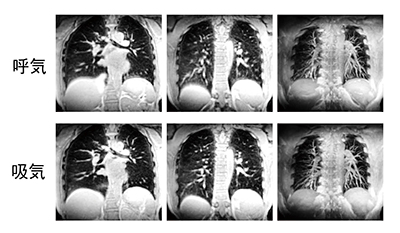

DWI撮像の技術的な問題点の一つとして,上記で触れたEPI収集による画像歪みがある。読み出し部分にシングルショットの高速スピンエコー法を用いてこれらの歪みをなくすことができるfast advanced spin-echo法DWI(以下,FASE-DWI)7)は,EPIでは難しかった頸部7)(図4)や肺野のDWIに用いられている。

図4 FASE-DWI頸部画像

撮像条件:FOV 22cm×22cm,マトリックス 112×128,ST=5mm,TE=80,TR=12500,b=600,FatSat ON,6軸 isotopic 収集,データ収集時間4:36。 頸部などの磁場不均一性が大きな部位でも,歪みなしに画像化可能。